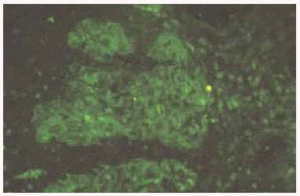

Se realizó biopsia de una de las lesiones, que mostró la existencia de una ligera acantosis de la epidermis y la presencia de pústulas subcórneas, junto con un moderado infiltrado inflamatorio de tipo mixto en la dermis superior (fig. 3). En la inmunofluorescencia directa se observaba depósito de IgA y C3 entre las células epidémicas subcórneas (fig. 4). La inmunofluorescencia indirecta fue negativa.

Fig. 4.--Depósito de IgA y C3 a nivel de los queratinocitos de capas superficiales.